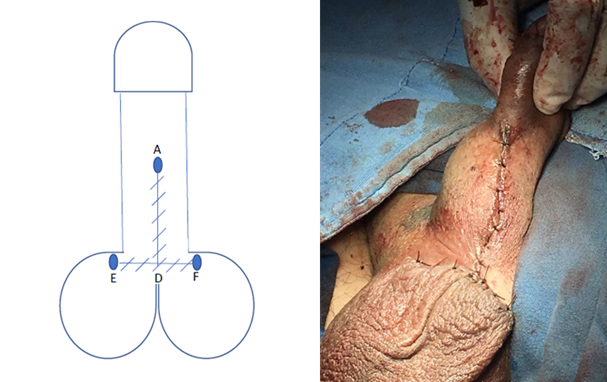

Se realiza protocolo prequirúrgico con documentación completa en el expediente clínico, ingreso del paciente para cirugía ambulatoria, con valoración anestésica, ayuno de 8 horas, baño previo al procedimiento, no se administró antibiótico profiláctico por no estar justificado, se realiza tricotomía según se necesite, se aplica asepsia antisepsia con iodopovidona. Se coloca lidocaína al 2% como anestésico local en el área quirúrgica en planos superficiales y profundos. La técnica quirúrgica aplicada en ambos casos se trata de una Plastia V-T, la cual consiste en realizar una incisión sobre la cuerda en forma de v invertida para despegar las capas de la piel de su adherencia aberrante en la cara ventral del pene (Figura 1 y 2), se afronta la nueva base del pene con sutura absorbible (Figura 3 y 4) , posteriormente se realiza incisiones laterales a la base del pene y coincidiendo a la raíz de la piel del escroto para distribuir toda la piel escrotal sobrante de manera uniforme, esto confiere la forma final de una T invertida (Figura 5 y 6).

Figura 3 Se realiza la incisión desde A a B y A a C, disecando las adherencias de la cuerda hasta la base del pene, quedando la piel del escroto redundante D.

Figura 4 Se sutura B con C para formar la nueva base del pene en su cara ventral y afrontando el resto de la piel del trayecto A con B-C, quedando la piel redundante, D, debajo.

Figura 5 Se trazan los puntos E y F lateralmente de la base del pene para ampliar la superficie de afrontamiento de la piel escrotal redundante y se sutura el escroto (D) a estas alas laterales (E y F)

Podemos observar que posterior a la realización de la circuncisión, se realizó paso a paso la técnica propuesta como podemos observar en las Figuras 1-6 que corresponden al caso 1 que fue el más representativo de la técnica.

En la técnica propuesta se logra respetar el sentido del rafe peneoescrotal, y el la incisión horizontal permite distribuir la ganancia de la piel escrotal de una manera uniforme para que cuando el pene este en erección, la dinámica de tensión en la piel tenga piel redundante en la base y evite la formación de pliegues a la tracción, además, en las imágenes se aprecia como se logra la separación total del pene del escroto, lo cual es uno de los principios básicos de la técnica quirúrgica (Figura 2), lo cual se logra como en ninguna otra descrita.